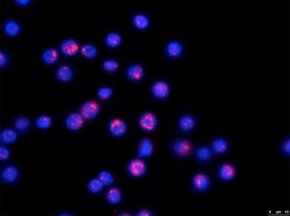

Novos antitumorais ativados por luz podem revolucionar tratamento contra o câncer

por

Imagem de capa: Autor desconhecido, encontrado na internet. Extraído de Oncolab Em tempos de culto à fosfoetanolamina, é sempre bom valorizarmos os novos tratamentos contra o câncer sendo desenvolvidos seguindo a metodologia correta. Um… Continuar lendo